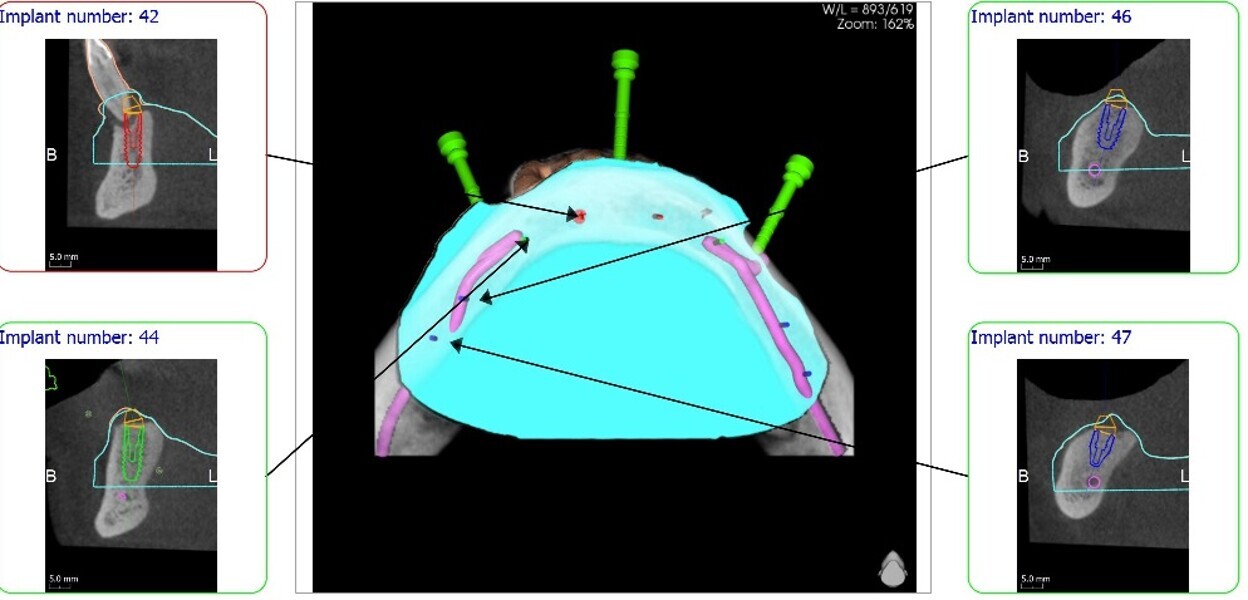

Implantacja z wykorzystaniem szablonu nawigacyjnego 3D